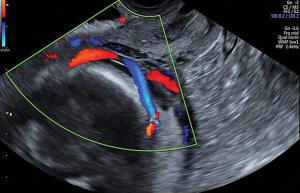

Identifying abnormal placentation is crucial for determining the correct management of at-risk pregnancies and minimizing morbidity and mortality of both mother and child.